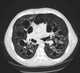

Tracheobronchomegaly is a very rare congenital disorder of the lung primarily characterized by an abnormal widening of the upper airways. The abnormally widened trachea and mainstem bronchi are associated with recurrent lower respiratory tract infection and copious purulent sputum production, eventually leading to bronchiectasis and other respiratory complications. [Source: Wikipedia ]